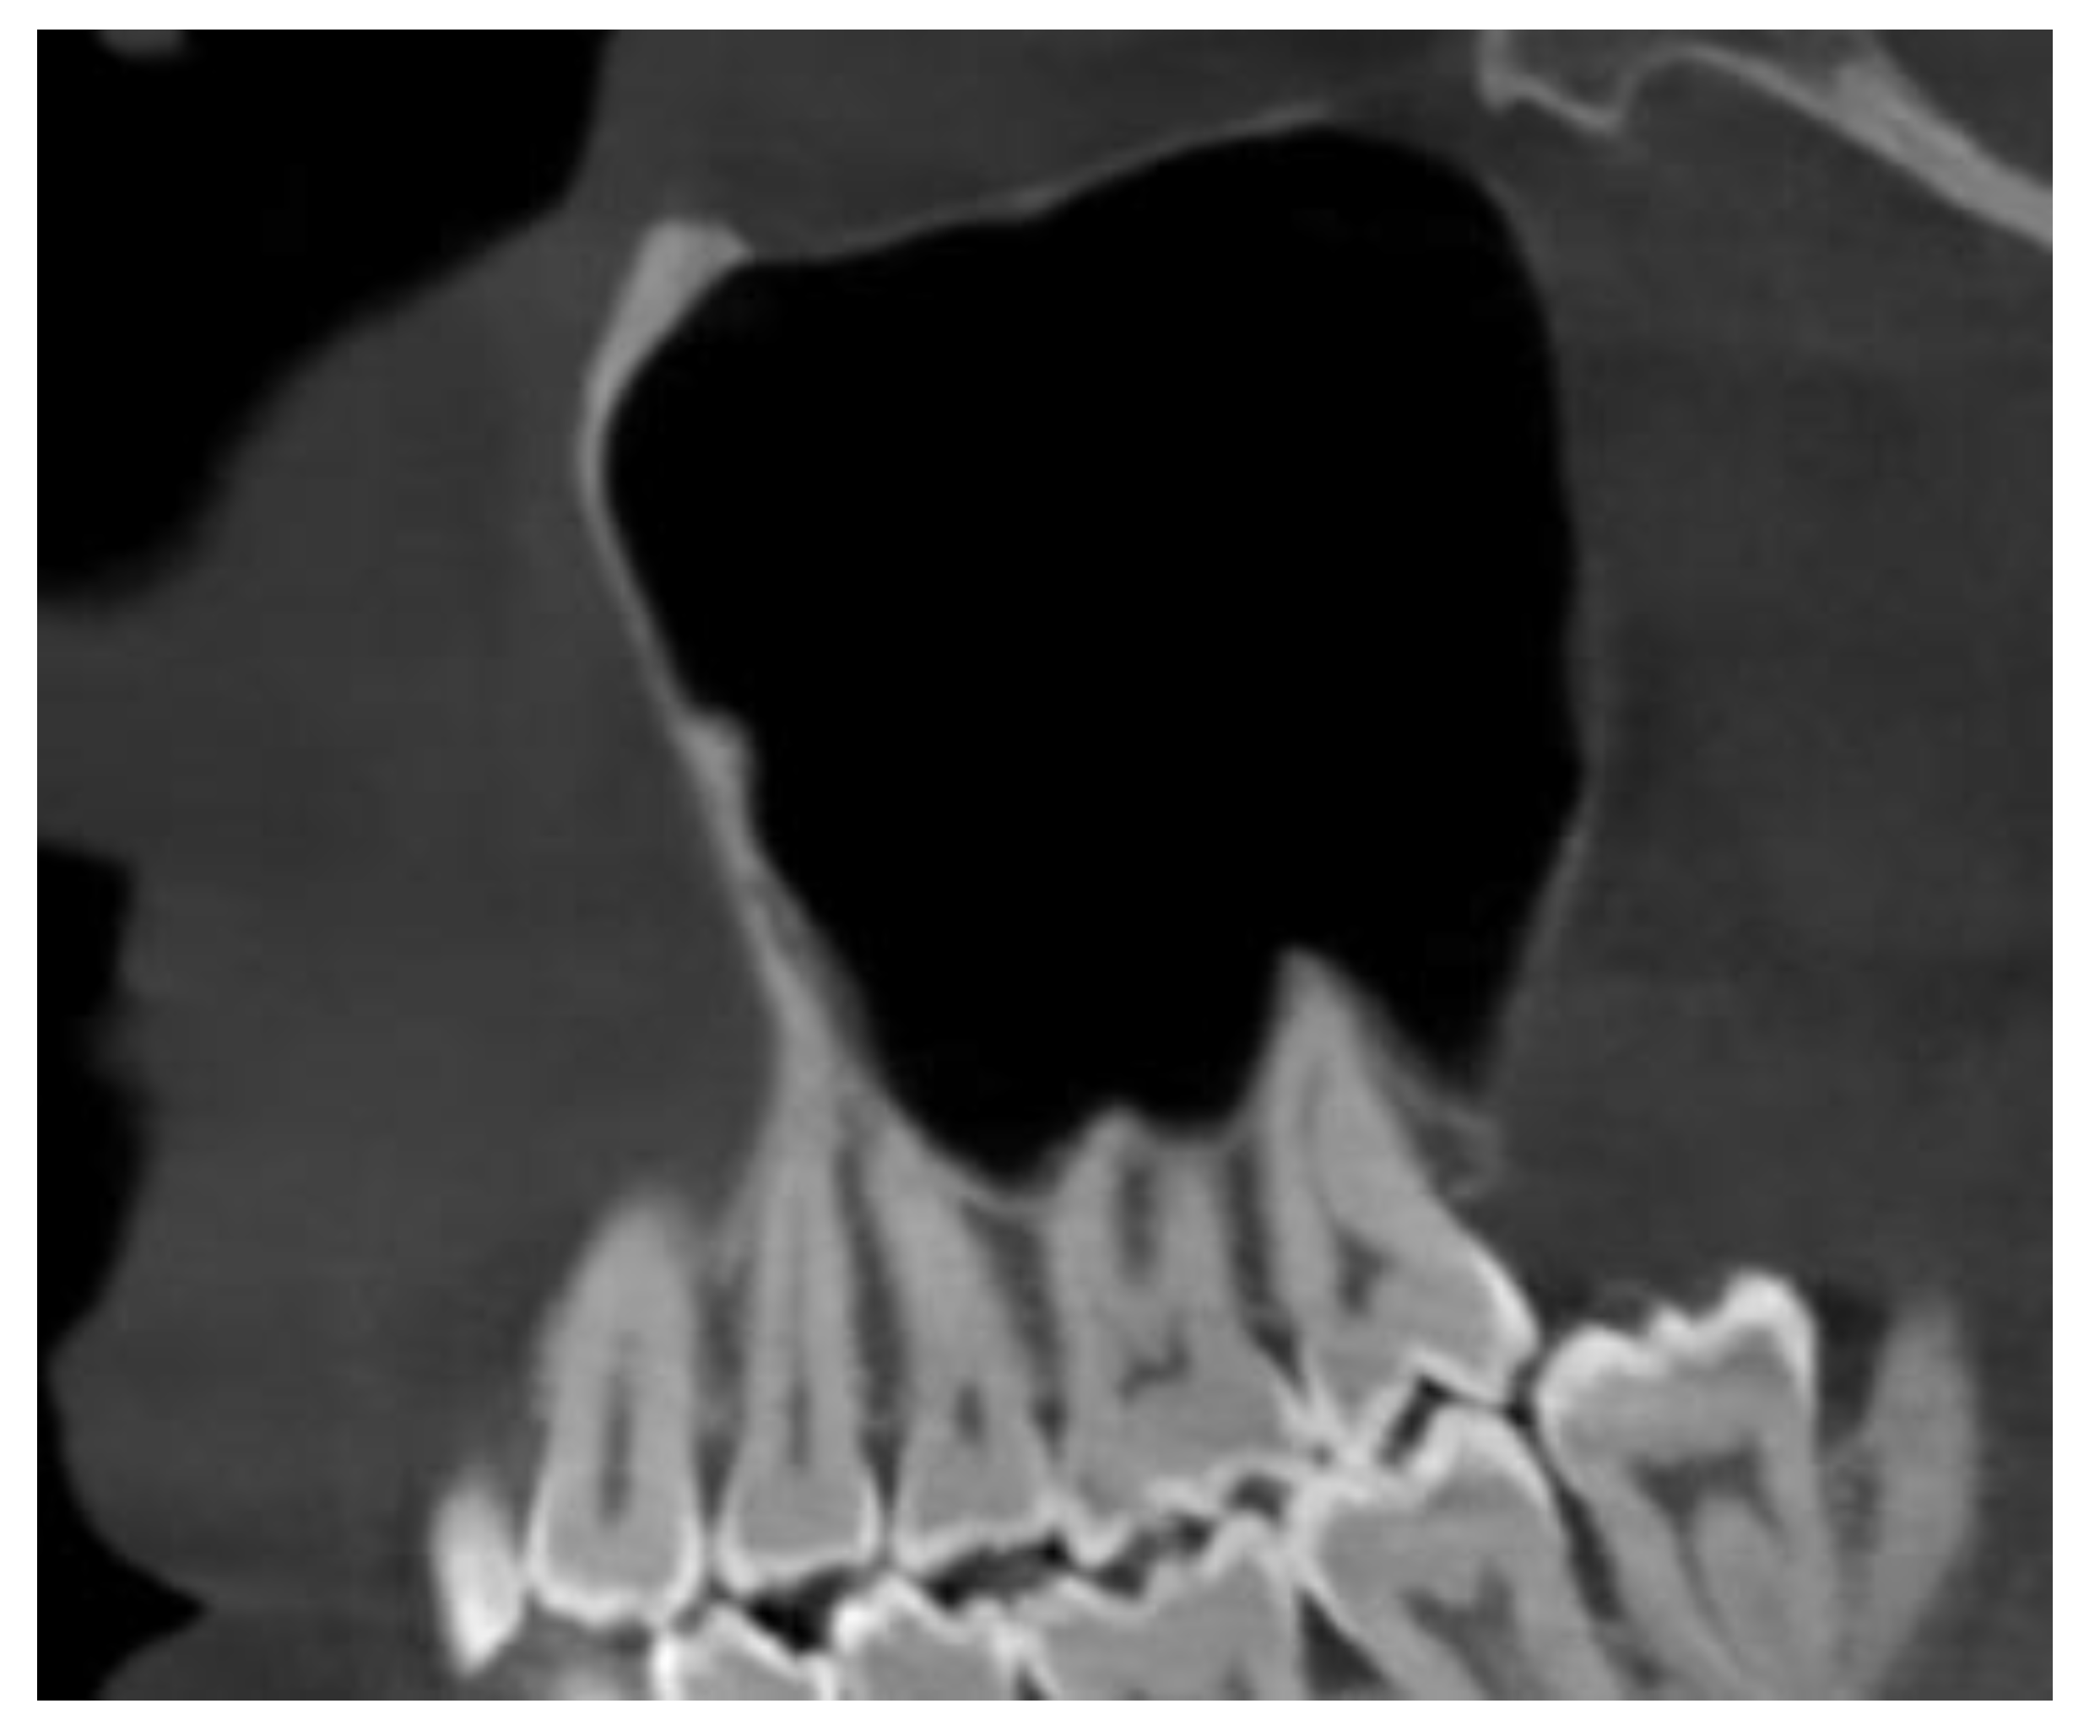

Maxillary Sinus

Septa